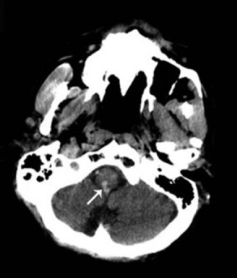

小脑出血小脑半球出血(左图),小脑蚓部出血(右图)

责任血管:多为齿状核动脉破裂

病因:高血压动脉硬化,小脑血管畸形,动脉瘤

症状体征: